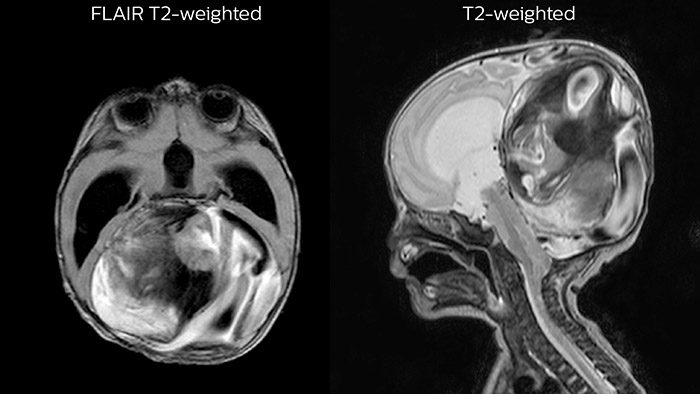

Leukodystrophy in a teenager

Since scan times of 3D scans can be significantly shortened thanks to Compressed SENSE, the MRI team is performing more 3D scans than before. “The advantage of 3D scanning is that we capture one high resolution sequence, but we can reconstruct images in any orientation, even after the scan, when looking at the images for diagnosis. Having this ability to view any crosssection we need in high resolution, can make re-scanning unnecessary,” says Dr Junge. “We are currently optimizing our routine head examination to include more 3D scans, including T1- weighted, T2-weighted and FLAIR.”

Features that provide remarkable benefits to Dr. Junge include Compressed SENSE, which allows to elevate spatial resolution, signal and scan time. MultiVane XD and 3D VANE XD employ radial k-space sampling and help to mitigate motion artifacts and improve robustness for different contrasts and for all age groups. The mDIXON FFE and mDIXON TSE methods nicely address challenges in fat-free imaging and provide multiple contrast types from one single scan. The achievable large field of view (FOV), high resolution and flexible echo times are certainly a huge benefit in examining children.